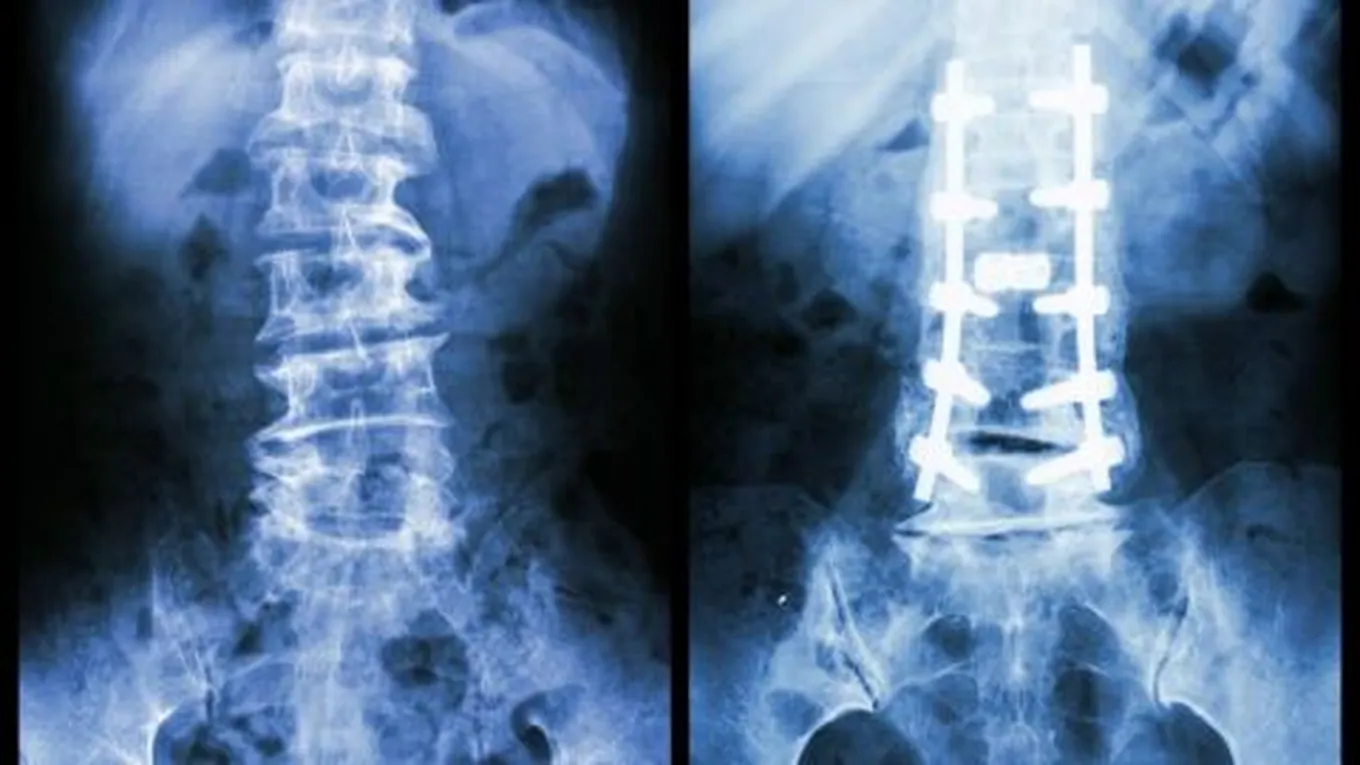

- إرجاع اجزاء العظم الى الوضع المقبول طبيا وتكون عملية الإرجاع اما بطرق مغلقة اوعن طريق تداخل جراحي

- تثبيت اجزاءالعظم في الوضع المقبول طبيا لحين التئام العظم وتكون عمليةالتثبيت اما عن طريق الجبائراوالمثبتات او اثقال متصلة بالطرف المصاب او عن طريق اجراء تداخل جراحي وتثبيت الكسر بواسطة الأسياخ او الصفائح المعدنية و خلال هذه الفترة يتم

التأهيل الطبيعي لمساعدة المصاب فيعودته لأداء وظيفته.